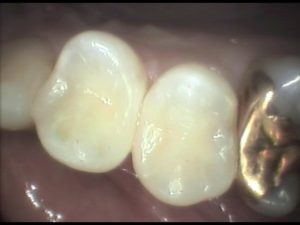

この患者さんは自由診療を選択されましたので、色や耐久性の良い素材を用いて、とても細かい部分までリアルな再現をしています。ちなみに費用は、小さなケースでしたので1本1万円で2年保証を付けています。(大きなものや複雑なものは1万5千円〜2万円)

麻酔も、早く切れるタイプを使っていますので、お帰りになる頃には通常どおりにお食事も可能です。銀歯を入れた時と違い、患者さんにとても喜んで頂き、こちらとしてもやりがいのある治療です。